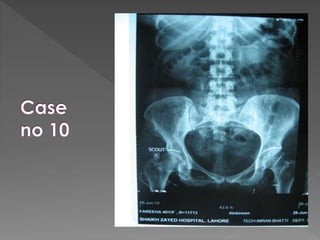

1) Pre contrast film “scout” film. (full length)

X ray films 1)Pre contrast 2) 5 mins 3) 25 mins 4) Post void